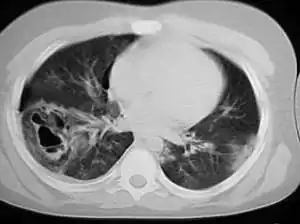

A chest CT scan revealing pulmonary contusions, pneumothorax, and pseudocysts